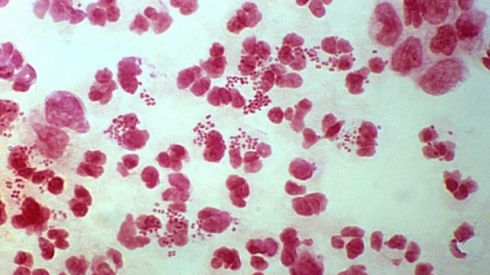

5. Обнаружили грибы CANDIDA и предложили лечить молочницу

Грибы в нормальном состоянии могут жить во влагалище, поэтому их наличие не говорит о наличии серьезных заболеваний и не свидетельствуют о молочнице.

А молочница характеризуется творожистыми выделениями, покраснение и отечностью, а также высыпаниями на коже и слизистых оболочках полового органа, при этом есть ощущение зуда, жжения особенно во время сна, после душа или полового акта.